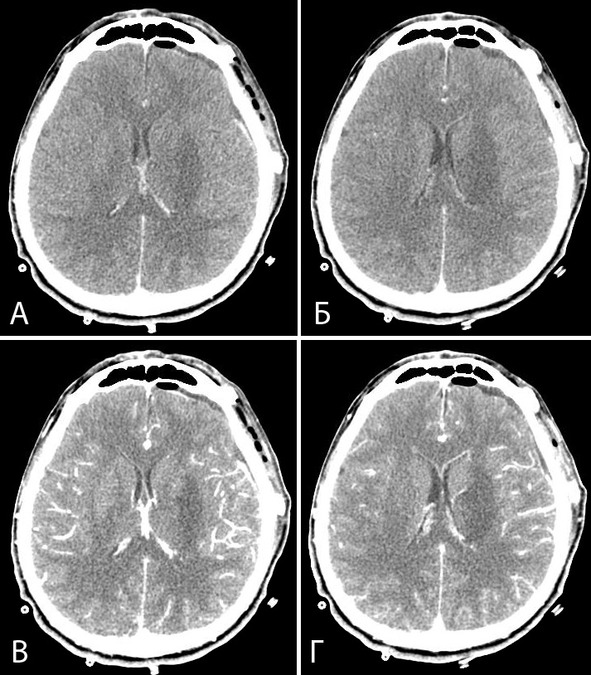

В послеоперационном периоде развилась симптоматика выраженного поражения подкорковых структур, диэнцефальной области и ствола мозга. Наблюдалось также нарушение ликвороциркуляции, подтвержденное при повторных КТ (рисунок 39) и потребовавшее длительного вентрикулярного дренирования. К течению болезни присоединился менинго-вентрикулит. На 22-й день после операции на фоне крайне тяжелого состояния больная умерла.

Рисунок 39. Клиническое наблюдение №7. Послеоперационная КТ, аксиальная проекция. Расширение желудочковой системы, пневмовентрикулоцефалия, скопление крови в области задних рогов боковых желудочков. Формирующиеся ишемические очаги в области подкорковых структур.

Патологоанатомическое заключение: Смерть больной наступила на 22-е сутки после операции субтотального «удаления кавернозной мальформации межжелудочковой перегородки, свода и 3 желудочка» и связана с нарушением мозгового кровообращения по смешанному типу в гипоталамусе, зрительных буграх в сочетании с отеком мозга с дислокацией и гипостатической пневмонией.